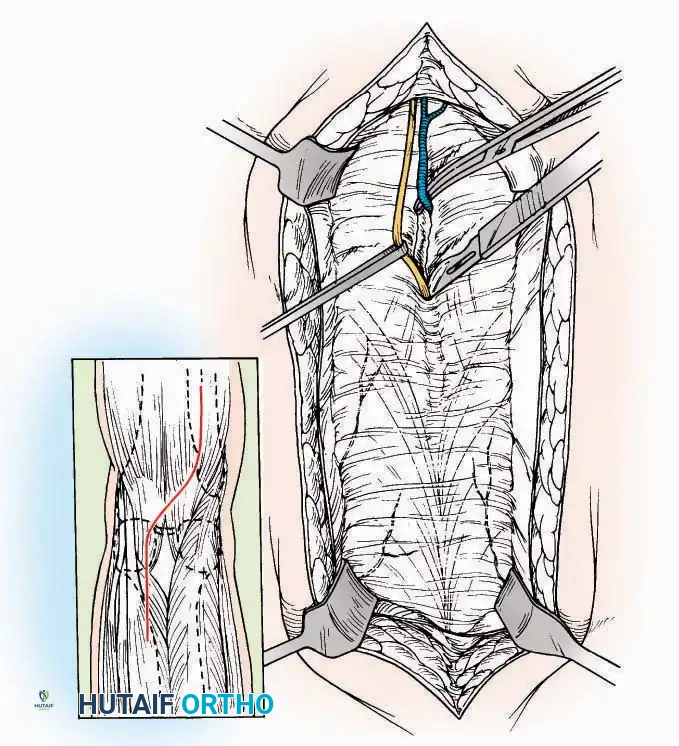

Anterior Approach

Indications: Total ankle arthroplasty (TAA), anterior ankle arthrodesis, and excision of anterior tibial/talar osteophytes (anterior impingement).

Surgical Technique:

* Incision: Make a 10 to 15 cm longitudinal incision over the anterior aspect of the ankle, centered exactly midway between the medial and lateral malleoli.

* Superficial Dissection: Incise the superficial fascia. Identify and protect the superficial peroneal nerve branches laterally and the saphenous nerve medially.

* Internervous Plane: The deep dissection exploits the plane between the Extensor Hallucis Longus (EHL) tendon (innervated by the deep peroneal nerve) and the Extensor Digitorum Longus (EDL) tendons (also innervated by the deep peroneal nerve).

* Neurovascular Bundle: Incise the extensor retinaculum. Carefully identify the anterior tibial artery and the deep peroneal nerve, which typically lie between the EHL and EDL, or directly deep to the EHL. Retract the neurovascular bundle laterally with the EDL, or medially with the EHL, depending on the specific anatomical variant encountered (lateral retraction is most common).

* Capsulotomy: Incise the anterior joint capsule longitudinally. Elevate the capsule subperiosteally from the anterior tibia and the talar neck to expose the entire tibiotalar articulation.